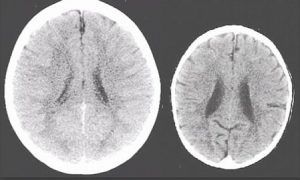

Neurologii au scanat creierul unui copil neglijat şi pe al unuia care are parte de afecţiunea mamei. Deşi ambii copii testaţi aveau trei ani, diferenţele constate au fost uimitoare. Creierul celui care nu a primit suficientă atenţie din partea mamei era considerabil mai mic decât normalul pentru vârsta lui şi îi lipsesc zone fundamentale.

Neurologii au scanat creierul unui copil neglijat şi pe al unuia care are parte de afecţiunea mamei. Deşi ambii copii testaţi aveau trei ani, diferenţele constate au fost uimitoare. Creierul celui care nu a primit suficientă atenţie din partea mamei era considerabil mai mic decât normalul pentru vârsta lui şi îi lipsesc zone fundamentale.